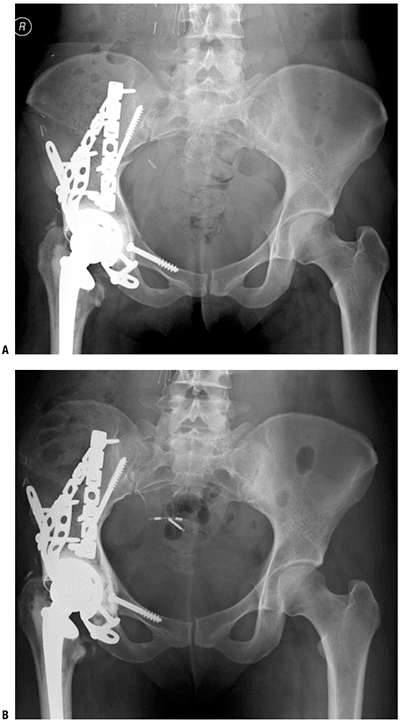

Rotationplasty requires preoperative planning to achieve both knees being at same level at skeletal maturity (see Fig. 4.3-9).P.67![]() Figure 4.3-8 After resection of an acetabular sarcoma, an allograft–prosthetic composite of the acetabulum was used for reconstruction. (A) Figure 4.3-8 After resection of an acetabular sarcoma, an allograft–prosthetic composite of the acetabulum was used for reconstruction. (A)

An anteroposterior (AP) radiograph soon after surgery shows the

acetabular cage and constrained cup cemented into the acetabular

allograft and the cemented femoral stem. The allograft is secured with

interfragmentary lag screws and pelvic reconstruction plates. (B) The allograft–host junctions are healed at 9 months postoperatively.P.68 Figure 4.3-9 Figure 4.3-9